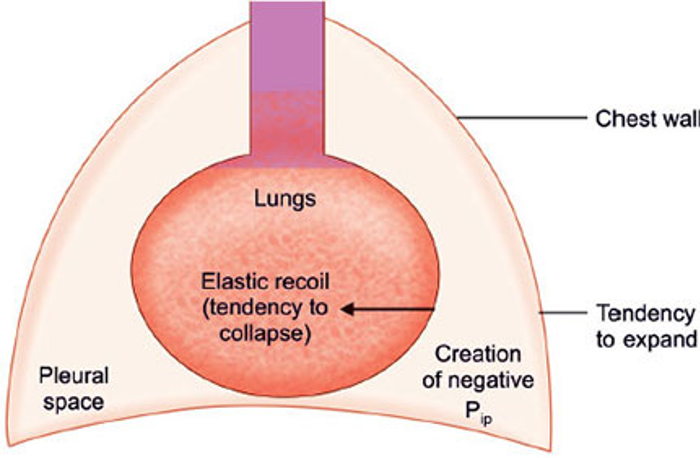

2/Let’s first start with some definitions. The term “non-expandable lung” is an umbrella term that is used to describe when the lung is unable to expand to the chest wall in order to achieve visceral and parietal pleura apposition. @AvrahamCooperMD @michellebr00ks @mdlizs

3/There are two pleural diseases that result in the “non-expandable lung”:

4/Lung entrapment is when the lung cannot fully expand due to an active disease that restricts the expansion of the lung and/or visceral pleura. This is typically associated with an exudative effusion. @tony_breu @KevinSwiatek

5/ Trapped lung is when the lung cannot expand due to a remote inflammatory condition that leaves a collagenous or fibrinous peel on the viscera pleura that prevents lung expansion. The pleural fluid can be transudative or exudative. @scall1200 @cderekleiner @rva_IntMedPD

12/In trapped lung, the fibrotic process affecting the visceral pleura causes an increase in the negative pleural pressure resulting in fluid accumulation and reduction in the removal of fluid by pleural lymphatics. @UpToDate @gsmartinmd @jackpenner